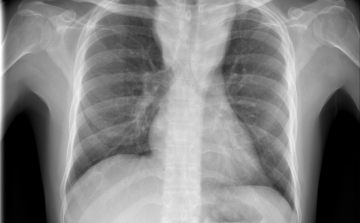

Terjed a tbc Szatymazon?

Hétfő reggel óta tbc-tesztet végeznek el a gyerekeken egy szatymazi általános iskolában, ahol egy hete fertőző tüdőbetegségben halt meg egy korábban ott dolgozó nő - közölték az M1 aktuális csatorna déli Híradójában.

Átlagosan 4,3 százalékkal csökkent az új tuberkulózisos (tbc-s) esetek száma 2010 és 2014 között az Egészségügyi Világszervezet (WHO) 53 országot magába foglaló európai régiójában.